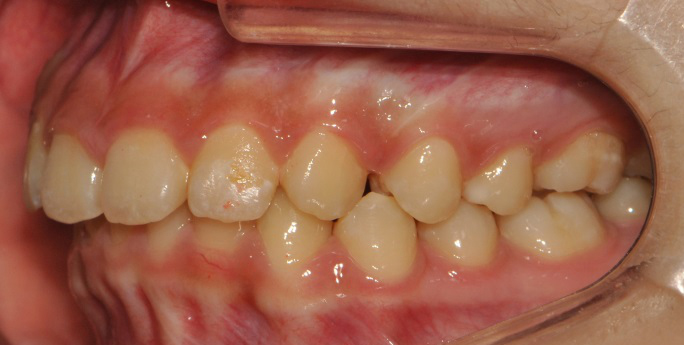

À§ ȯÀÚ´Â À´Ï°¡ ¾Æ·§´Ï¸¦ ³Ê¹« µ¤¾î¿ä(°ú°³±³ÇÕ) ¸¦ ÁÖ¼Ò·Î ³»¿øÇÑ ÃʵîÇлýÀ̾ú½À´Ï´Ù. ÅμºÀå ¾ÇÁ¤ÇüÀåÄ¡ »ç¿ëÈÄ È£ÈíÀÌ °³¼± µÇ¾úÀ¸¸ç Ä¡·áÀü¿¡ ºñÇØ ۰¡ 10cmÁ¤µµ ±Þ¼Ó ¼ºÀåÇÏ¿´½À´Ï´Ù.

°ú°³±³ÇÕ°ú ¹«ÅÎ,ÅΰüÀýÀ» ÁÖ¼Ò·Î ³»¿øÇÏ¿© ÅμºÀå ¾ÇÁ¤ÇüÀåÄ¡¸¦ ÀÌ¿ëÇÏ¿© Ä¡·áÁßÀΠȯÀÚ·Î Ä¡·á½ÃÀÛ½ÃÁ¡ ±âÁØÀ¸·Î ÇöÀç ۰¡ ¾à 8cmÁ¤µµ ¼ºÀåÇÏ¿´½À´Ï´Ù. (Âü°í·Î 2³âÂ÷ ¿©µ¿»ý°ú ۰¡ 7-9cmŰ Â÷À̳²)